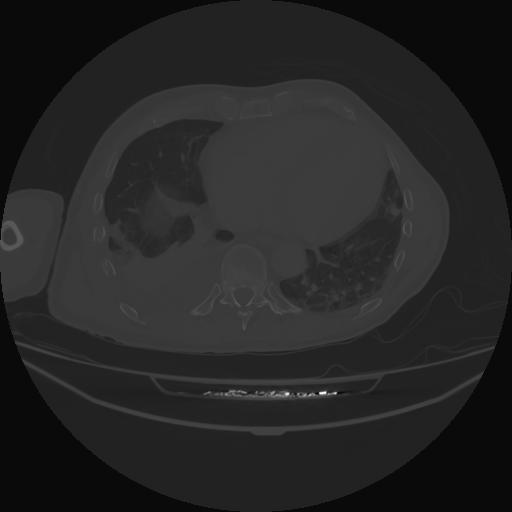

5 CUERPO,CE,Vol,1.0,CUERPO,,